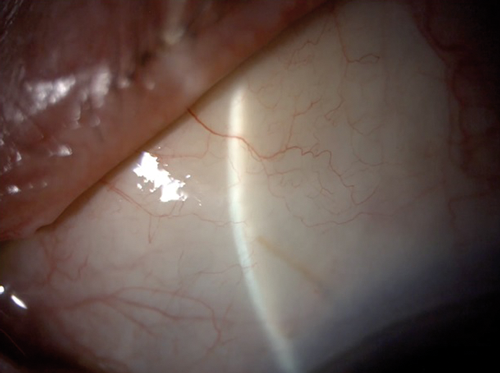

Attempts have been made to try to mimic the results of canal-based surgery in a minimally invasive fashion. The Hydrus Microstent, as previous mentioned, claimed not only to bypass TM resistance, but also to dilate and scaffold the canal. Early histological evidence supported this theory [18] and the most recent study by Gandolfi et al. demonstrated very similar efficacy between the Hydrus Microstent and canaloplasty [19], although it was a retrospective comparison rather than a RCT. Ab-interno canaloplasty (ABiC) is a procedure where, similarly to the GATT procedure, an illuminated micro-catheter (iTrack, Ellex, Adelaide, Australia) is passed circumferentially into Schlemm’s canal ab-internally under gonioscopic guidance. However, instead of tearing out through the TM, the micro-catheter is retracted backwards while viscoelastic is injected into the canal. The aim is to viscodilate the canal and unblock the collector channels by potentially releasing herniated TM (Figure 3).

Figure 3: Ab-interno canaloplasty - micro-catheter is being withdrawn

while viscoelastic is injected into the Schlemm’s canal.

The illuminated tip is visible at 10 o’clock position at the limbus.

Whether the efficacy of ABiC approaches that of viscocanalostomy remains to be proven, as there are no peer-reviewed published clinical outcomes of this procedure so far. A white paper issued by the manufacturers based on the surgical outcomes of surgeons in two centres on 228 patients, claimed a reduction in IOP from 19mmHg on two medications to 13.3mmHg on one medication at 12 months, with combined cataract surgery not significantly affecting the outcome [20].